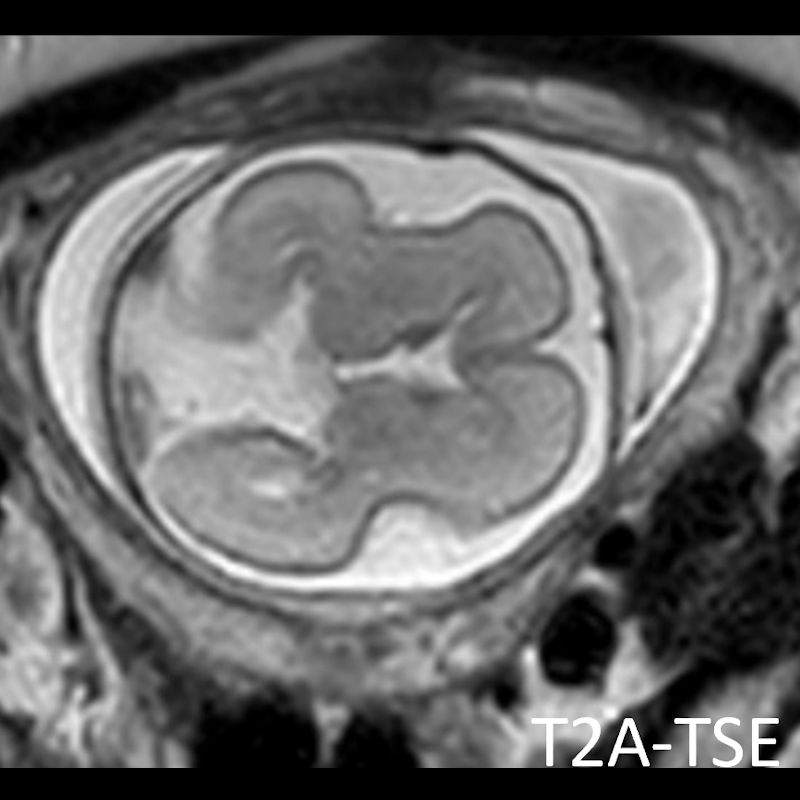

- A) USG incelemede serebral kortikal yapılar düzleşmiş (ok), gyrus sayısı azalmıştır (ok). Kalın ve ekojenik korteks mevcut olup korteks -beyaz cevher ayrımı silik görünümdedir. Posterior fossada ekstraaksiyel BOS mesafesi artmış görünümdedir (ok).

- B) Aksiyel ve sagittal T2A görüntülerde gyrus ve sulkuslarda azalma mevcut olup korteks kalınlaşmış görünümde ve operkulizasyon ayırt edilememiştir. Korteks beyaz cevher ayrımı zor seçilmektedir (ok) Ekstraaksiyel BOS mesafesi artmış görünümdedir (ok). Yapılan ölçümlerde; tegmentovermian açı :8 derece (ok) serebellar vermis boyutları kraniokaudal: 16 mm, aksiyel: 5,5×8,5 mm (ok) ölçülmüş olup BPD:27w ile uyumlu olan fetüste haftasıyla uygun olarak değerlendirilmiştir.

- Gri/beyaz cevher oranı beyaz cevher aleyhine azalmıştır.

- Operkulizasyon yokluğuna bağlı sylvian fissürün açık görünümü ve vertikal yerleşimi karakteristik bir bulgudur. Serebral yapılar; sığ ve vertikal yerleşimli sylvian fissür sebebiyle “8” görünümündedir. Ancak bu görünümün 26. gestasyonel haftaya kadar normal olduğu akılda tutulmalıdır.

- İnsula açıkta olup klastrum ve eksternal kapsül bulunmayabilir. Beynin gross görünümü fetüste sulkusların oluşmaya başladığı 20. gestasyonel haftayla benzer görünümdedir.